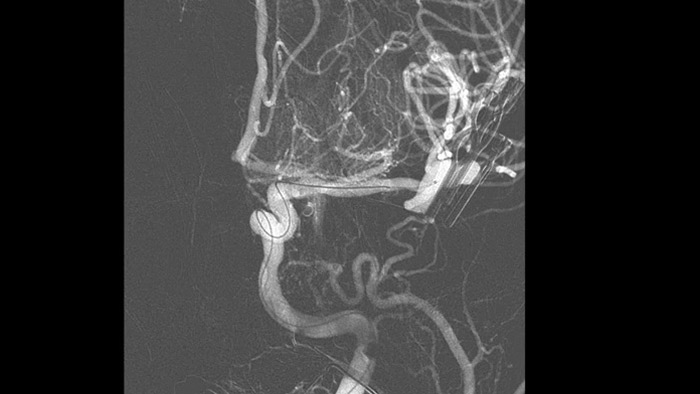

Технология SmartCT Roadmap улучшает визуализацию перекрывающихся сосудов, способствуя точному управлению проводником и катетером при их проведении через сложные сосудистые структуры. Данная технология обеспечивает высокую точность операции, компенсируя при этом в режиме реального времени артефакты движения С-дуги, стола и небольших движений пациента.

Усовершенствованная технология Roadmap Pro способствует улучшению визуализации перекрывающихся сосудов, сохраняя при этом баланс дозовой нагрузки. Во время установки спирали для эмболизации данное приложение можно настроить для наблюдения за продвижением.